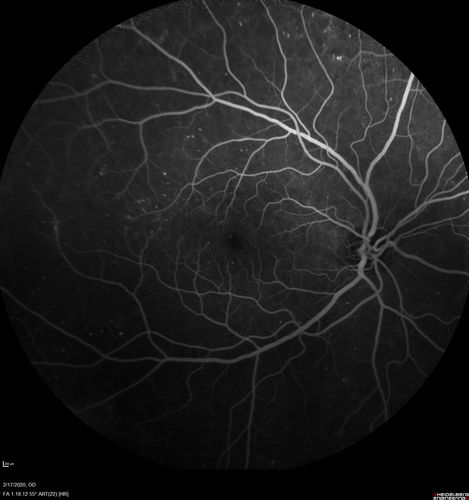

PDR and Vitreous Hemorrhage - High Risk Left Eye - Low Risk Right Eye

50 year old man with type I diabetes mellitus for 26 years. New Vitreous Hemorrhage in the left eye. Both eyes have NVE. Both also have foveal hypoplasia